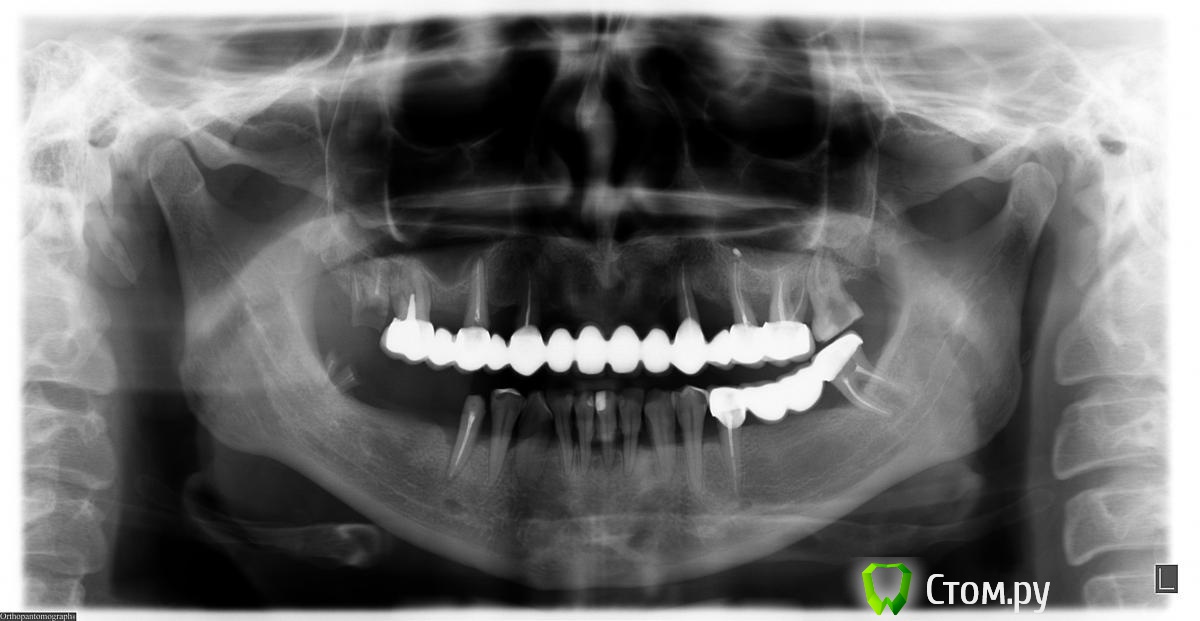

Алексшем Опубликовано 24 декабря, 2013 Поделиться Опубликовано 24 декабря, 2013 (изменено) Были у нескольких врачей.Один говорит что можно имплантировать без увеличения кости на верхней челюсти. Другой сказал что обязательно нужно увеличить кость. Я без передних верхних зубов с 12 лет,сейчас мне 36 лет.Посоветуйте, какие варианты возможны в моём случае?какую технику лечения лучше применить? Добавляю снимок! Изменено 24 декабря, 2013 пользователем Алексшем 1 Ссылка на комментарий

IvanK Опубликовано 25 декабря, 2013 Поделиться Опубликовано 25 декабря, 2013 Какие-то варианты пластики понадобятся. Больше можно сказать при очном осмотре и анализе КТ 1 Ссылка на комментарий